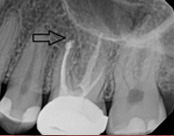

This person presented with one root that had failed from root canal treatment. The arrow in the picture, shows the infection as well as extra filling material that was pushed out of the root. An apical microsurgery was performed using the laser. The infection and excess material was cleaned out. Complete healing is visible 3 months after. The tooth was saved. This is a poor area for an implant.